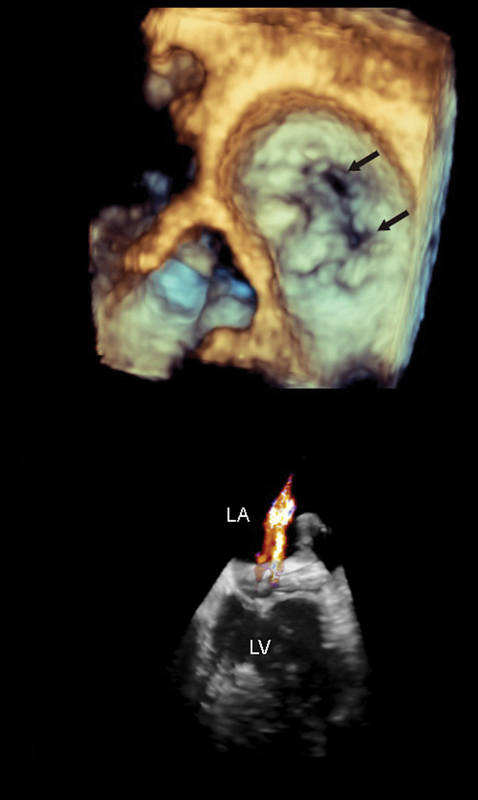

فحوصات تشخيصية لبعض امراض القلب والشرايين التاجية